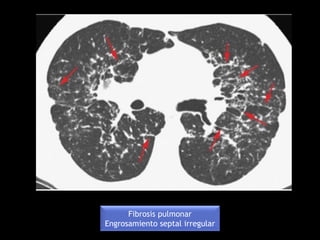

Fibrosis pulmonar

Engrosamiento septal irregular